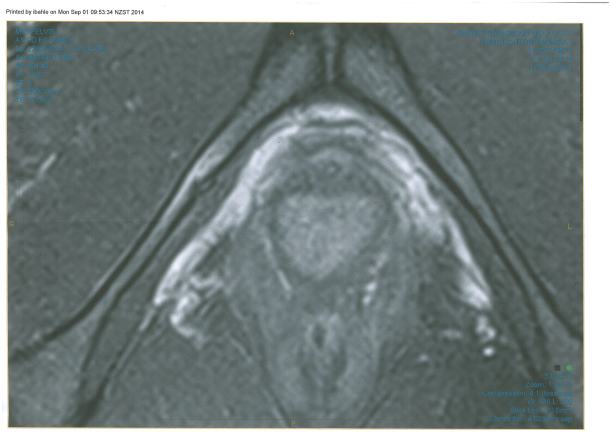

OSTEITIS PUBIS- an overuse injury characterised by tissue damage and inflammation to the pelvis at the site where the two pubic bones join, resulting in sharp pain right down the centre of your fajita. It is caused by repeated trauma, such as running 140km a week, however, it is not uncommon for a specific incident to trigger the symptoms.